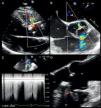

A 36-year-old man was referred to our hospital for a recent finding of a heart murmur. He had no relevant medical history except paroxysmal palpitations in the previous three months. Physical examination revealed a high-grade continuous rumbling murmur best heard at the left sternal border. Initial transthoracic echocardiography showed continuous flow between the aorta and the right ventricle (RV) (Figure 1A). The subsequent transesophageal echocardiogram (TEE) confirmed the presence of a tubular, windsock-like communication 4.5 mm in diameter between the right sinus of Valsalva (RSV) (displayed deformed) and the RV (Figure 1B and 1D, Video 1), with an effective regurgitant orifice of 0.11 cm2 in color flow Doppler (according to proximal isovelocity surface area measurement) and a systolic-diastolic flow in continuous wave Doppler (Figure 1C). There was also moderate aortic regurgitation (grade 3/4), with an eccentric jet directed toward the anterior mitral leaflet. Real-time three-dimensional (RT3D) TEE demonstrated the tubular morphology of the ruptured sinus (enlarged) and the direction of flow described above (Figure 2A and B, Video 2). Finally, multiplanar reconstruction color flow three-dimensional TEE showed a vena contracta area calculated by direct planimetry of 0.09 cm2 (Figure 2C). The patient underwent surgical defect closure with monofilament suture, leaving mild aortic regurgitation on intraoperative TEE.

(A) Transthoracic color Doppler echocardiography, parasternal long axis view, showing a continuous flow from the aorta to the right ventricle (arrow). (B) Transesophageal color Doppler echocardiography, mid-esophageal plane at 51°, showing the jet of the fistula (arrow) and moderate eccentric aortic regurgitation. (C) Continuous wave Doppler showing systolic-diastolic flow at the fistula level (arrow). (D) Transesophageal echocardiography, mid-esophageal plane at 124° (zoomed in on the aorta), showing a tubular communication between the right sinus of Valsalva and the right ventricle (arrow). Ao: aorta; LA: left atrium; LV: left ventricle; RA: right atrium; RV: right ventricle.